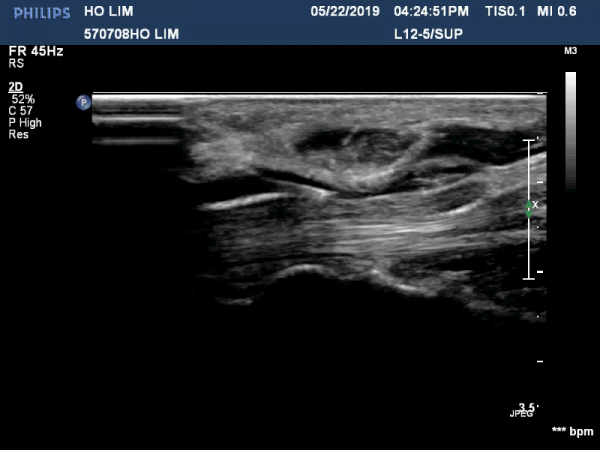

4 sono.jpg

¼Õ¸ñ ºÎÀ§¿¡¼­ Á¤Á߽Űæ Ⱦ´Ü¸é°Ë»ç»ó Á¤Á߽ŰÜÀÇ Àú¿¡ÄÚ ºÎÁ¾ÀÌ °üÂûµÊ(»çÁø 1).